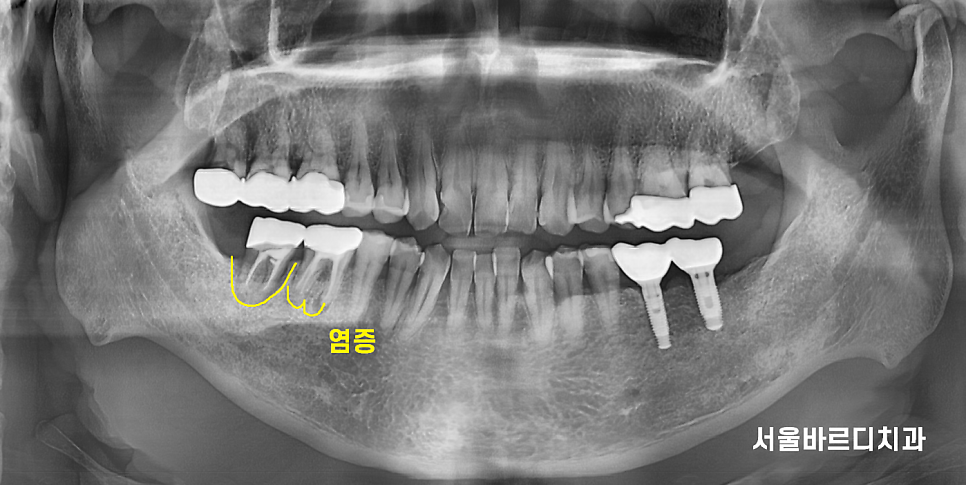

치아 뿌리 끝 염증은 주로 x ray 촬영을 통해 발견됩니다.

x-ray를 보여드려도 체감을 잘 못하세요~

평면 x ray보다 사실적인

3d ct를 보여드리겠습니다.

240418

뼈는 하얗게 보여야하는데요.

뿌리 염증으로 잇몸뼈를 녹이면

까맣게 변합니다.

뼈가 그만큼 없어지니까요~